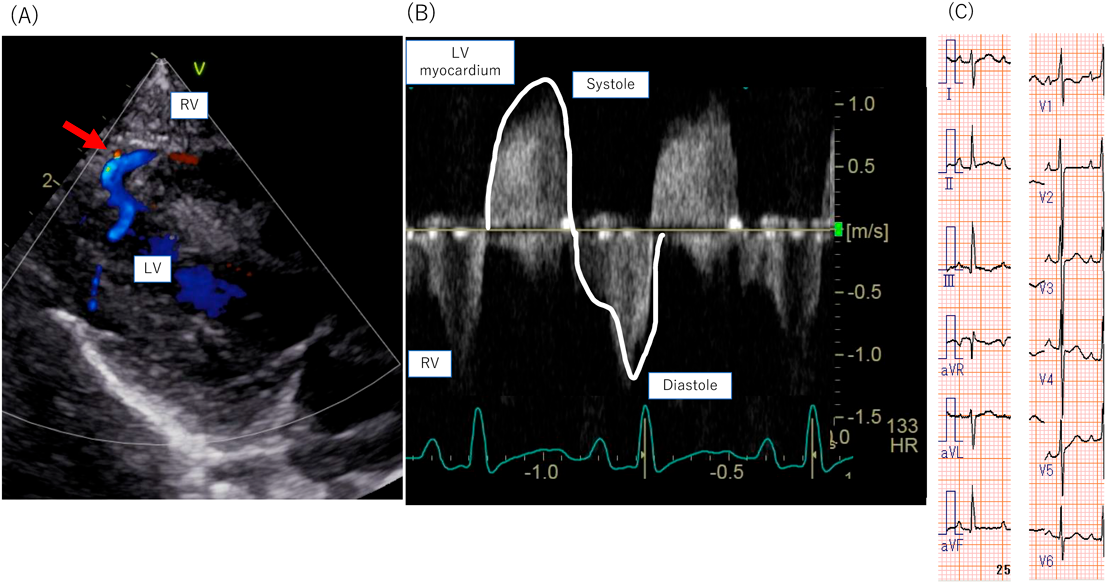

右室依存性冠循環を伴った右心低形成症候群に対する上行大動脈右室短絡術前後の冠血流評価Evaluation of Coronary Perfusion Using Pulsed-Wave Doppler in Hypoplastic Right Heart Syndrome with Right Ventricle-Dependent Coronary Circulation Before and After Aorta-To-Right Ventricle Shunt